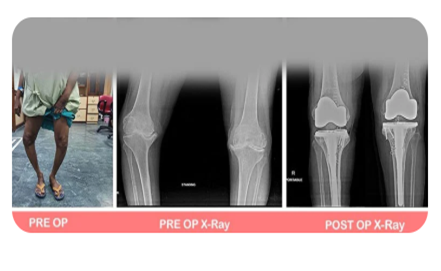

Complex Knee & Hip Replacement Surgeries

Our surgeons are highly experienced in handling complex cases like bow legs (varus), knock knees (valgus), or wind-swept legs, and have considerable expertise in revision joint replacement surgeries.